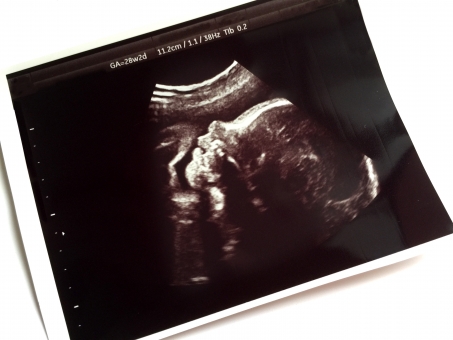

妊娠30週目のお腹の胎児の体重は、およそ平均して1000グラムから1500グラムほどになっています。エコー検査で見る胎児は新生児で生まれた赤ちゃんに比べるとまだ肉付きは薄く体重も少なく、見た目はとても華奢に見えます。

お腹の中の胎児は妊娠30週目頃から少しずつお母さんの体からもらった栄養を自分の体に蓄えていきます。残りの10週の妊娠期間で胎児の体重はさらに増え、エコー検査で見る胎児の見た目もふっくらと愛らしい体型に変化していきます。

お腹の胎児の体重は大きさと同じく、平均値に入っていないからといって不安に思う必要は全くありません。産婦人科の医師のもとで妊娠中の定期検診やエコー検査などをきちんと受けているのであれば、胎児に何か病気や異常があればすぐに分かるものです。

もしエコーなどを見ていて気になることがある時は、その場で医師に確認して不安を取り除いてもらうと良いですね。胎児がお腹の中で元気に手足を動かしている様子が分かれば安心できます。

妊娠30週目のお腹の胎児の体の機能はほぼ完成しています。胎児は水を飲んだり排泄を行うことも出来るようになり、エコーを見ると頻繁に目をパチパチとして瞬きをしたりあくびをしたりしている様子を確認することができます。

エコーで見る胎児の様子はもう普通の赤ちゃんそのものといった感じで、ここ数カ月の間に見違えるほど身体機能が向上したことが伺えます。

さらに妊娠30週を超えた胎児はエコーで見ると、お母さんのお腹の中で外からの明かりにも敏感に反応することが分かっています。そのためお母さんが夜更かしをして夜はお昼過ぎまで寝ているような不規則な生活を送っていると、お腹の中の赤ちゃんが混乱してしまって睡眠のリズムがつきにくいと考えられています。